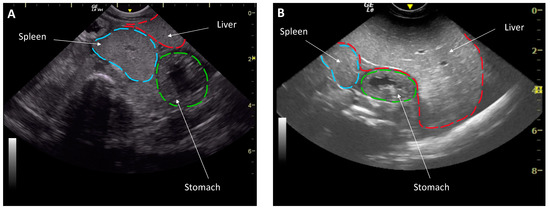

- Mylniczenko, N.D.; Penfold, L.M.; Guttridge, T.L.; Wyffels, J.T. Ultrasound comparison of the liver to spleen as an evalustion of liver and body condition in elasmobranchs. In Proceedings of the American Association of Zoo Veterinarians, Prague, Czech Republic, 6 October 2018. [Google Scholar]